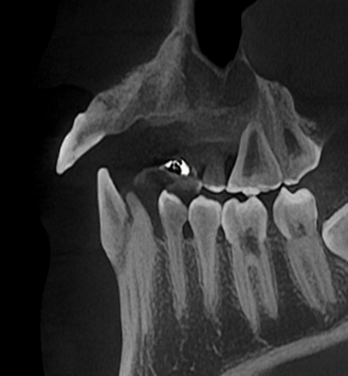

CT 촬영으로 뼈 상태와

치은 상태를 정확히 확인합니다.

뼈가 많이 녹았다면

이를 뽑을 때 또는

일정 시간 후에 뼈이식을 합니다.

충분한 뼈가 있어야

임플란트를 심을 수 있고

앞니는 자연스러운 모양을

만드는 것이 중요합니다.